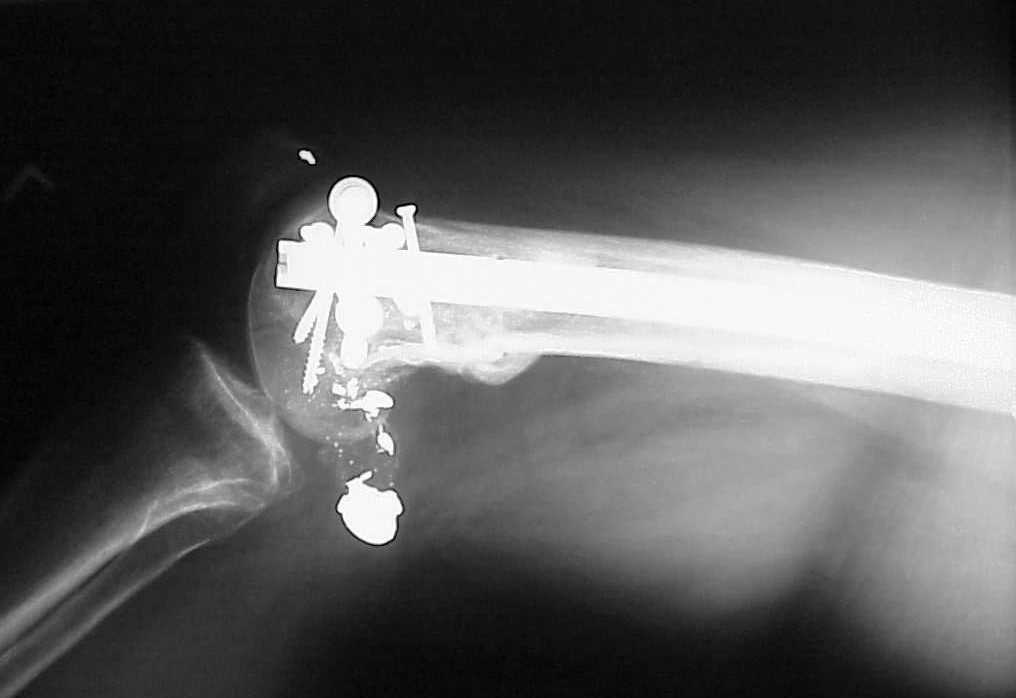

See attached case that was done several years ago before LISS. He had comminuted trochlea and anterior blocking screws were used to prevent anterior IMN cut-out.

Use 6.5 mm cannulated screws if you have and

place one anterior to where IMN will go if anterior cortex if insufficient and AP screws on either side of the IMN out of the trochlea to provide some additional varus/valgus stability. I worry about the leg going into valgus w/the lack of lateral cortex.